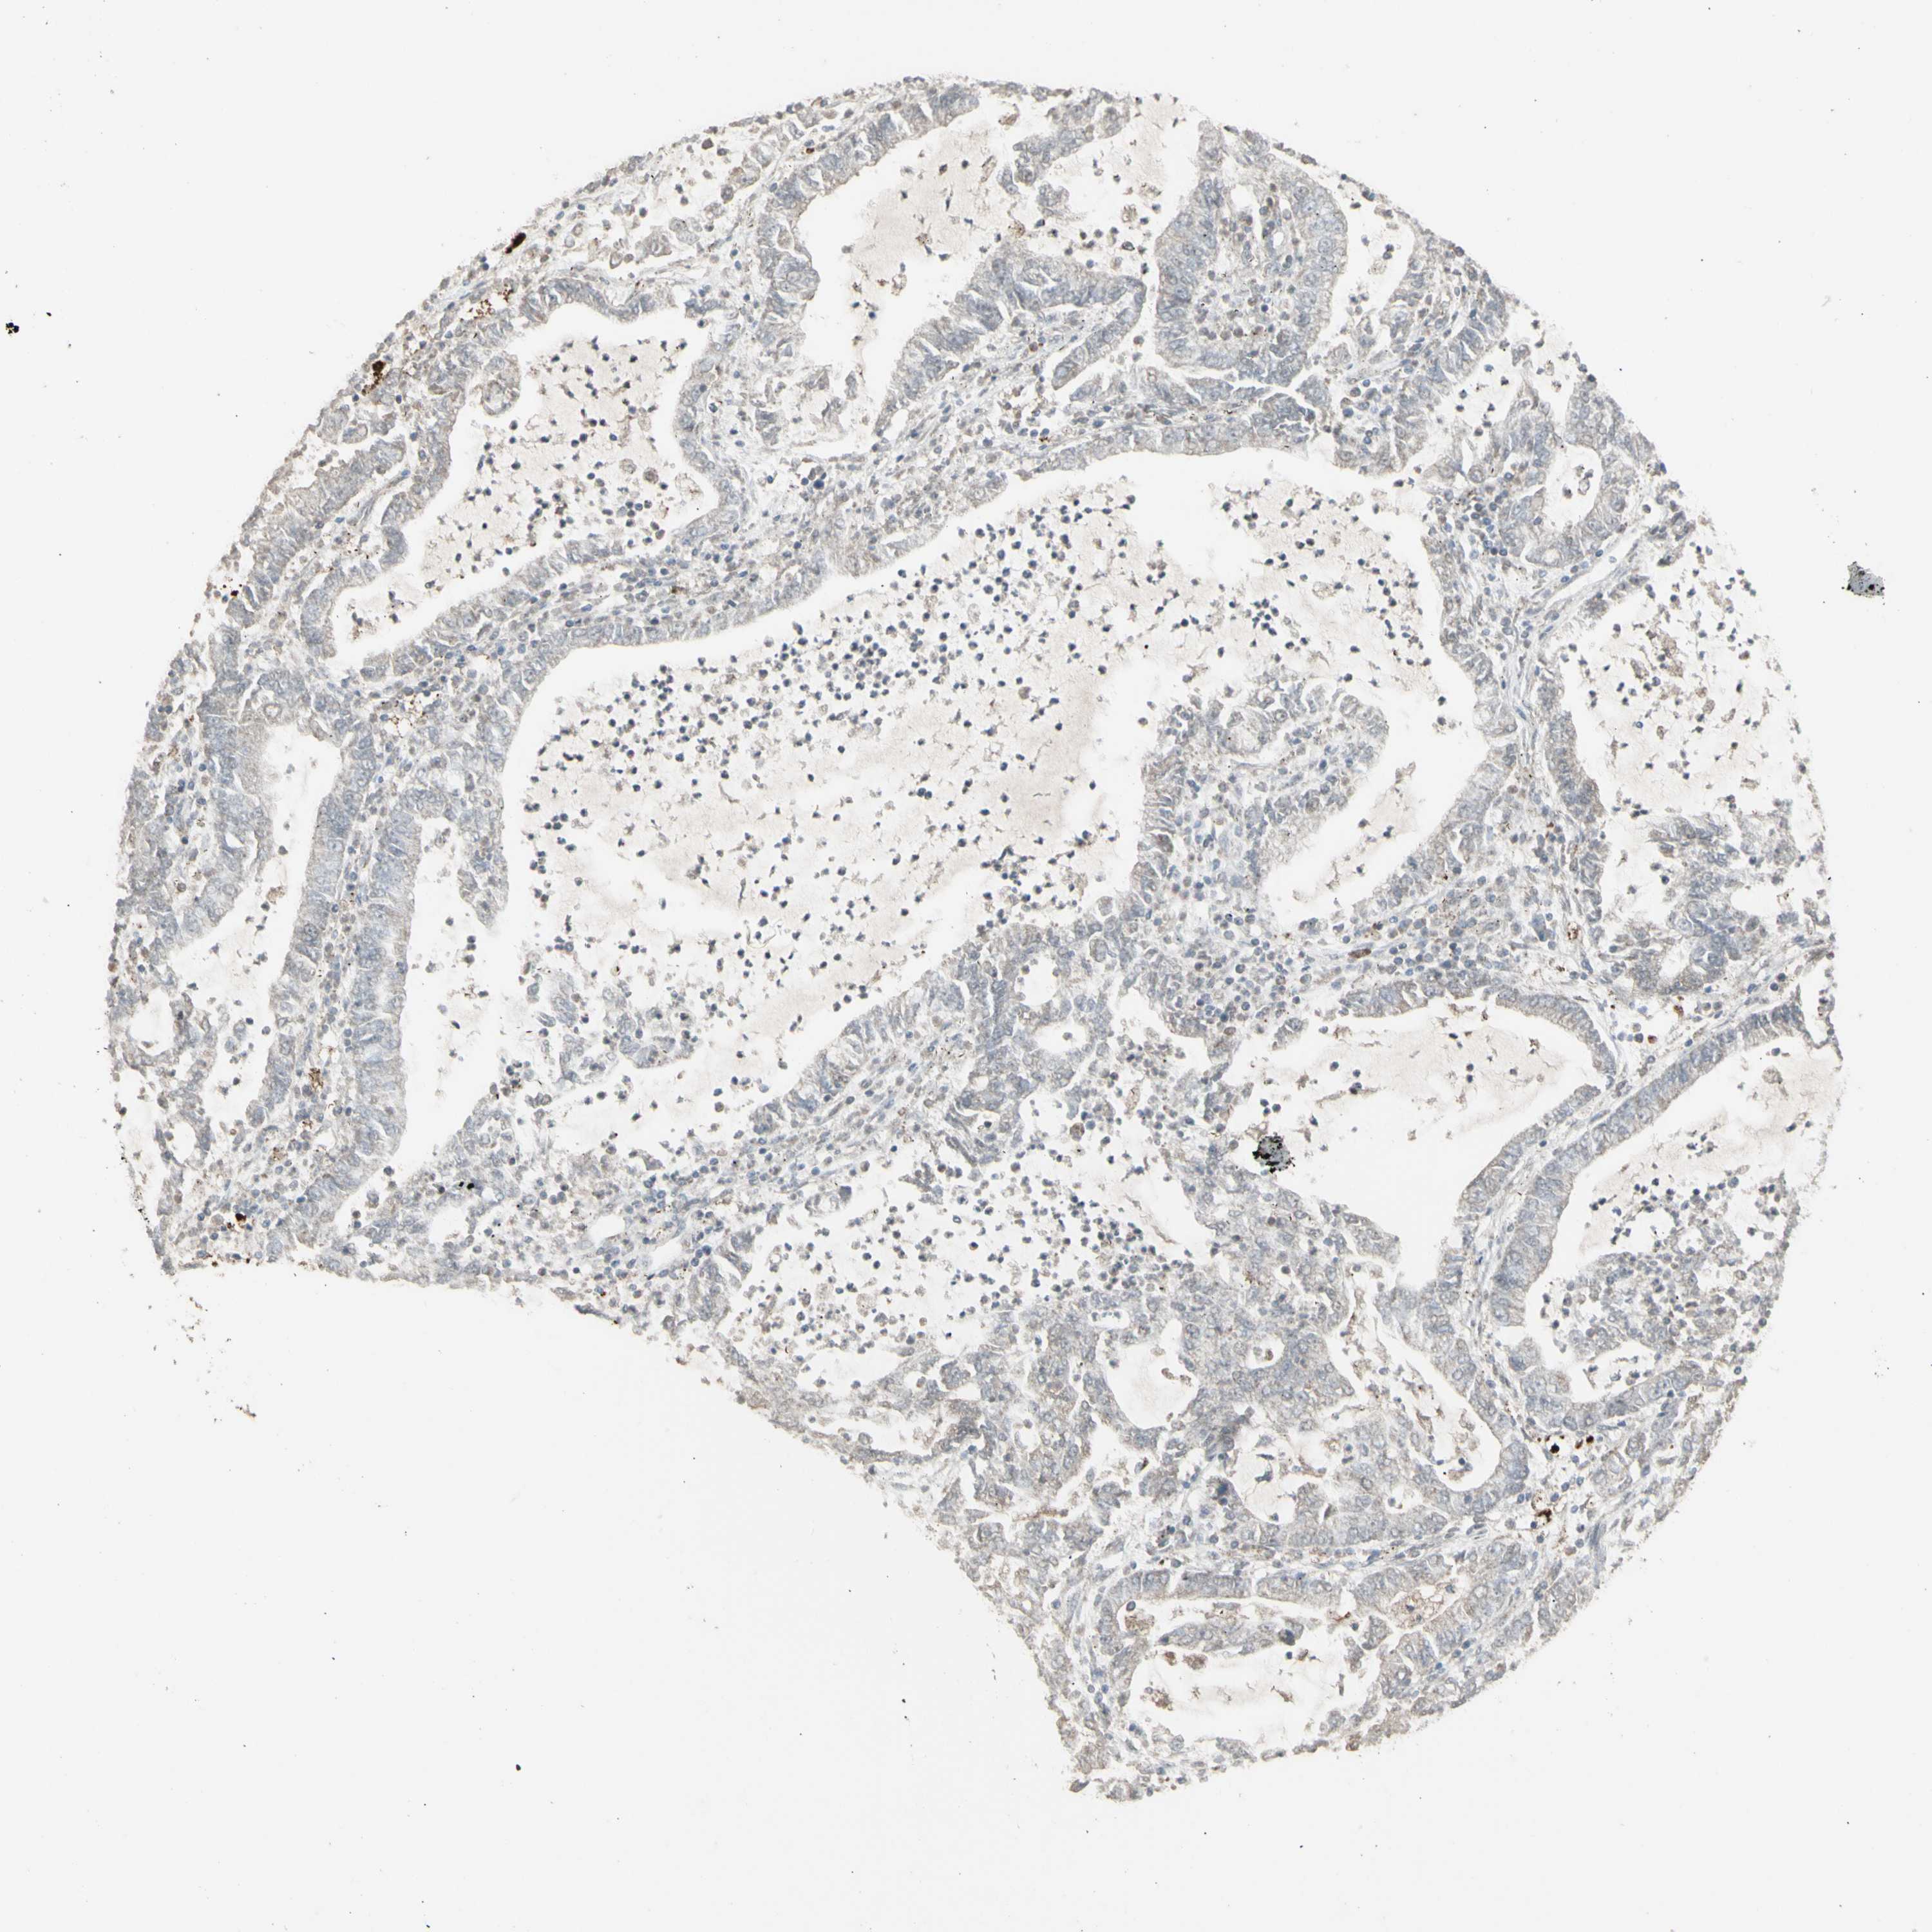

CANCER LUNG CANCER Show tissue menu

LUAD TCGA LUAD VALIDATION LUSC TCGA LUSC VALIDATION PROTEIN LUAD CPTAC PROTEIN LUSC CPTAC PROTEIN EXPRESSION